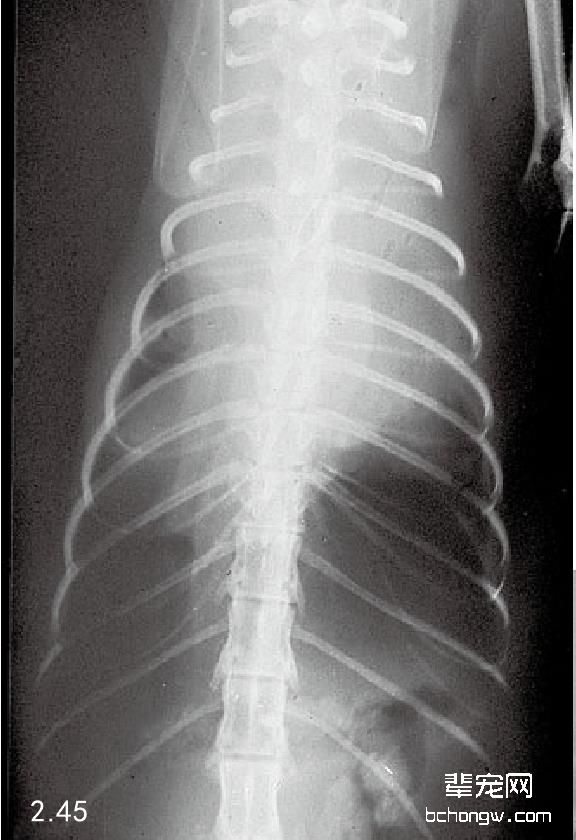

X线检查 侧面影像中,前部胸腔纵隔肿块引起气管偏离,心脏后侧移位和前侧心脏边缘消失;在背腹侧影 像中前部纵隔增宽和肺前叶后侧移位(图2.44和图2.45)。胸腔壁肿瘤通常引起软组织膨胀,导致邻近的肋骨移 位,作为额外的胸膜肿块延伸进入胸腔(图2.46和图2.47)。

图2.45 与图2.44同只猫的背腹侧胸腔X线片。